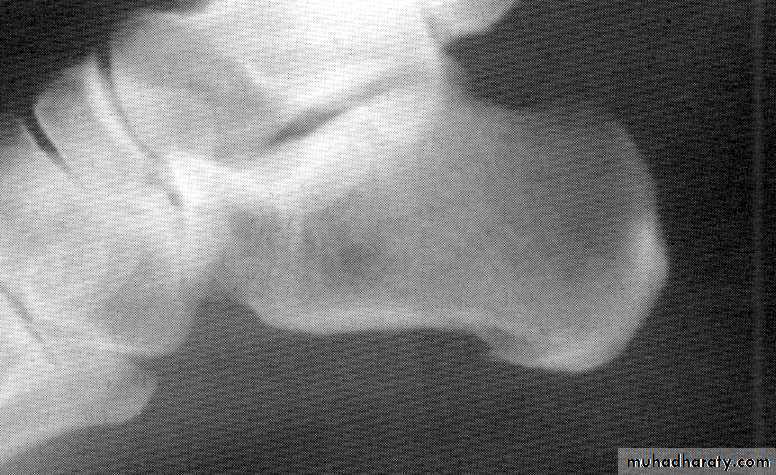

3- X-ray: the typical radiographic changes of RA are periarticular osteopenia& marginal non proliferative erosions.